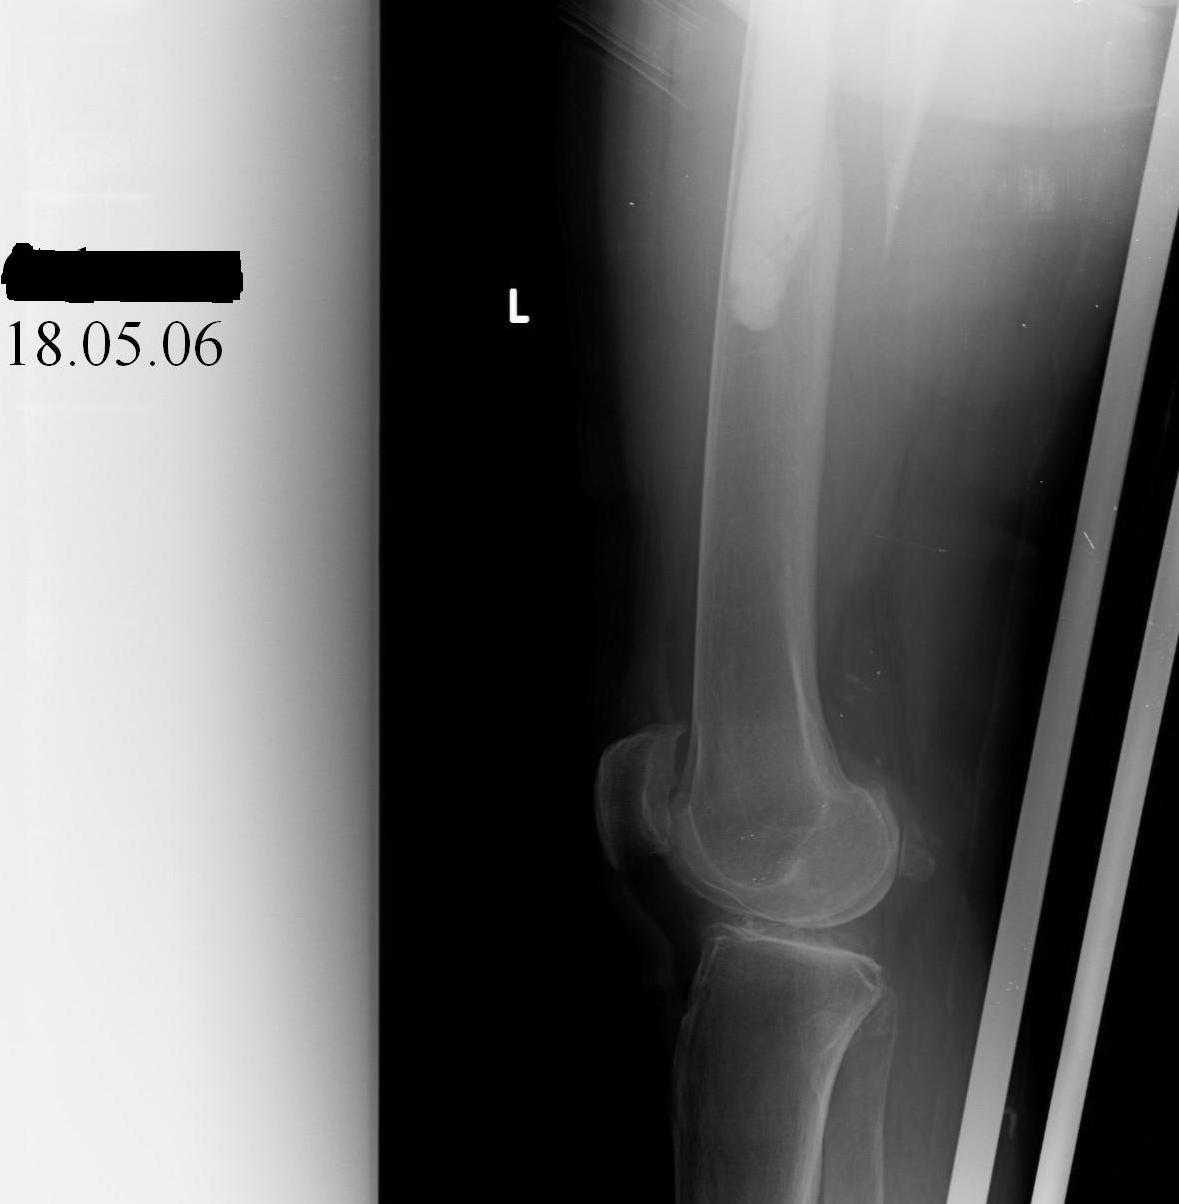

Female, rheumatoid, THA in 2003, car accident in 2006, failed plating. Nailing in Oct 2007. The nail is solid with hollow proximal part where the stem is docked. Last images are in 1 year after

nailing.